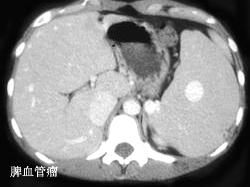

选项 A、脾脏脓肿 B、脾血管瘤 C、肝硬化并发脾肿大 D、某些血液疾病 E、外伤性脾破裂

答案 ABCDE